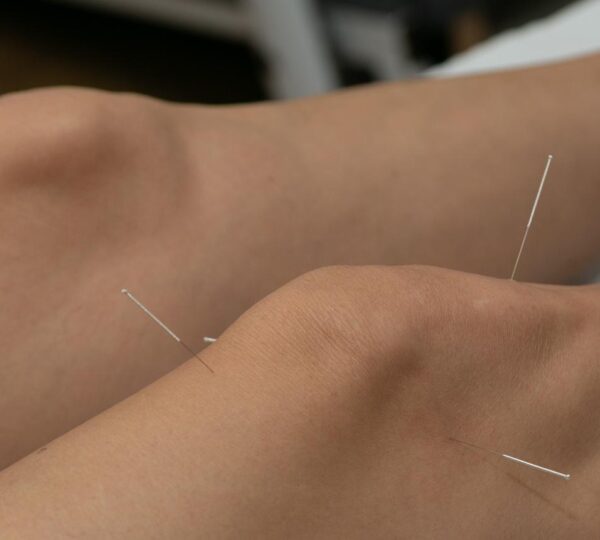

Frustrated by limited results from medications, she turned to alternative therapies. Acupuncture, a centuries-old practice rooted in traditional Asian medicine, was her next option, and it promised potential pain relief without the gastrointestinal issues.

Acupuncture involves inserting fine needles into specific points on the body to relieve pain or improve overall health. In some traditional practices, tiny pieces of gold are used instead of standard stainless steel needles.

In her case, the needles—believed to be gold—were left inside her knees intentionally. This practice, known as intradermal or retained acupuncture, is intended to provide continuous stimulation to the joint and prolong therapeutic effects.

While retained acupuncture is relatively rare, it remains a common approach for arthritis treatment in parts of Asia. Practitioners believe that the constant stimulation helps reduce joint pain and inflammation over time.